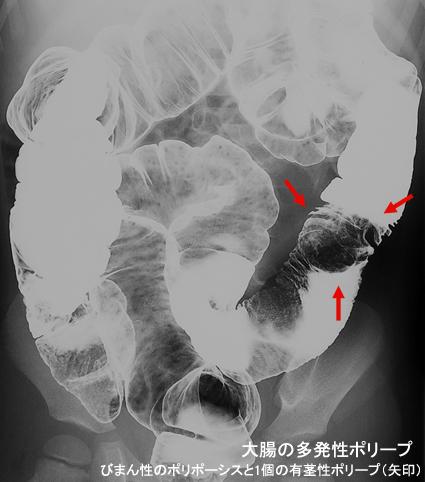

A case of juvenile polyposis which multiple polypoid lesions were found in the stomach and intestine.

종양양 병변/연소성 용종증

부위(장기별)

대장/2구역 이상의 대장에 걸치는 것

1형(종괴형)/

25~29

다발종양(동일 장기)

유(동시성)